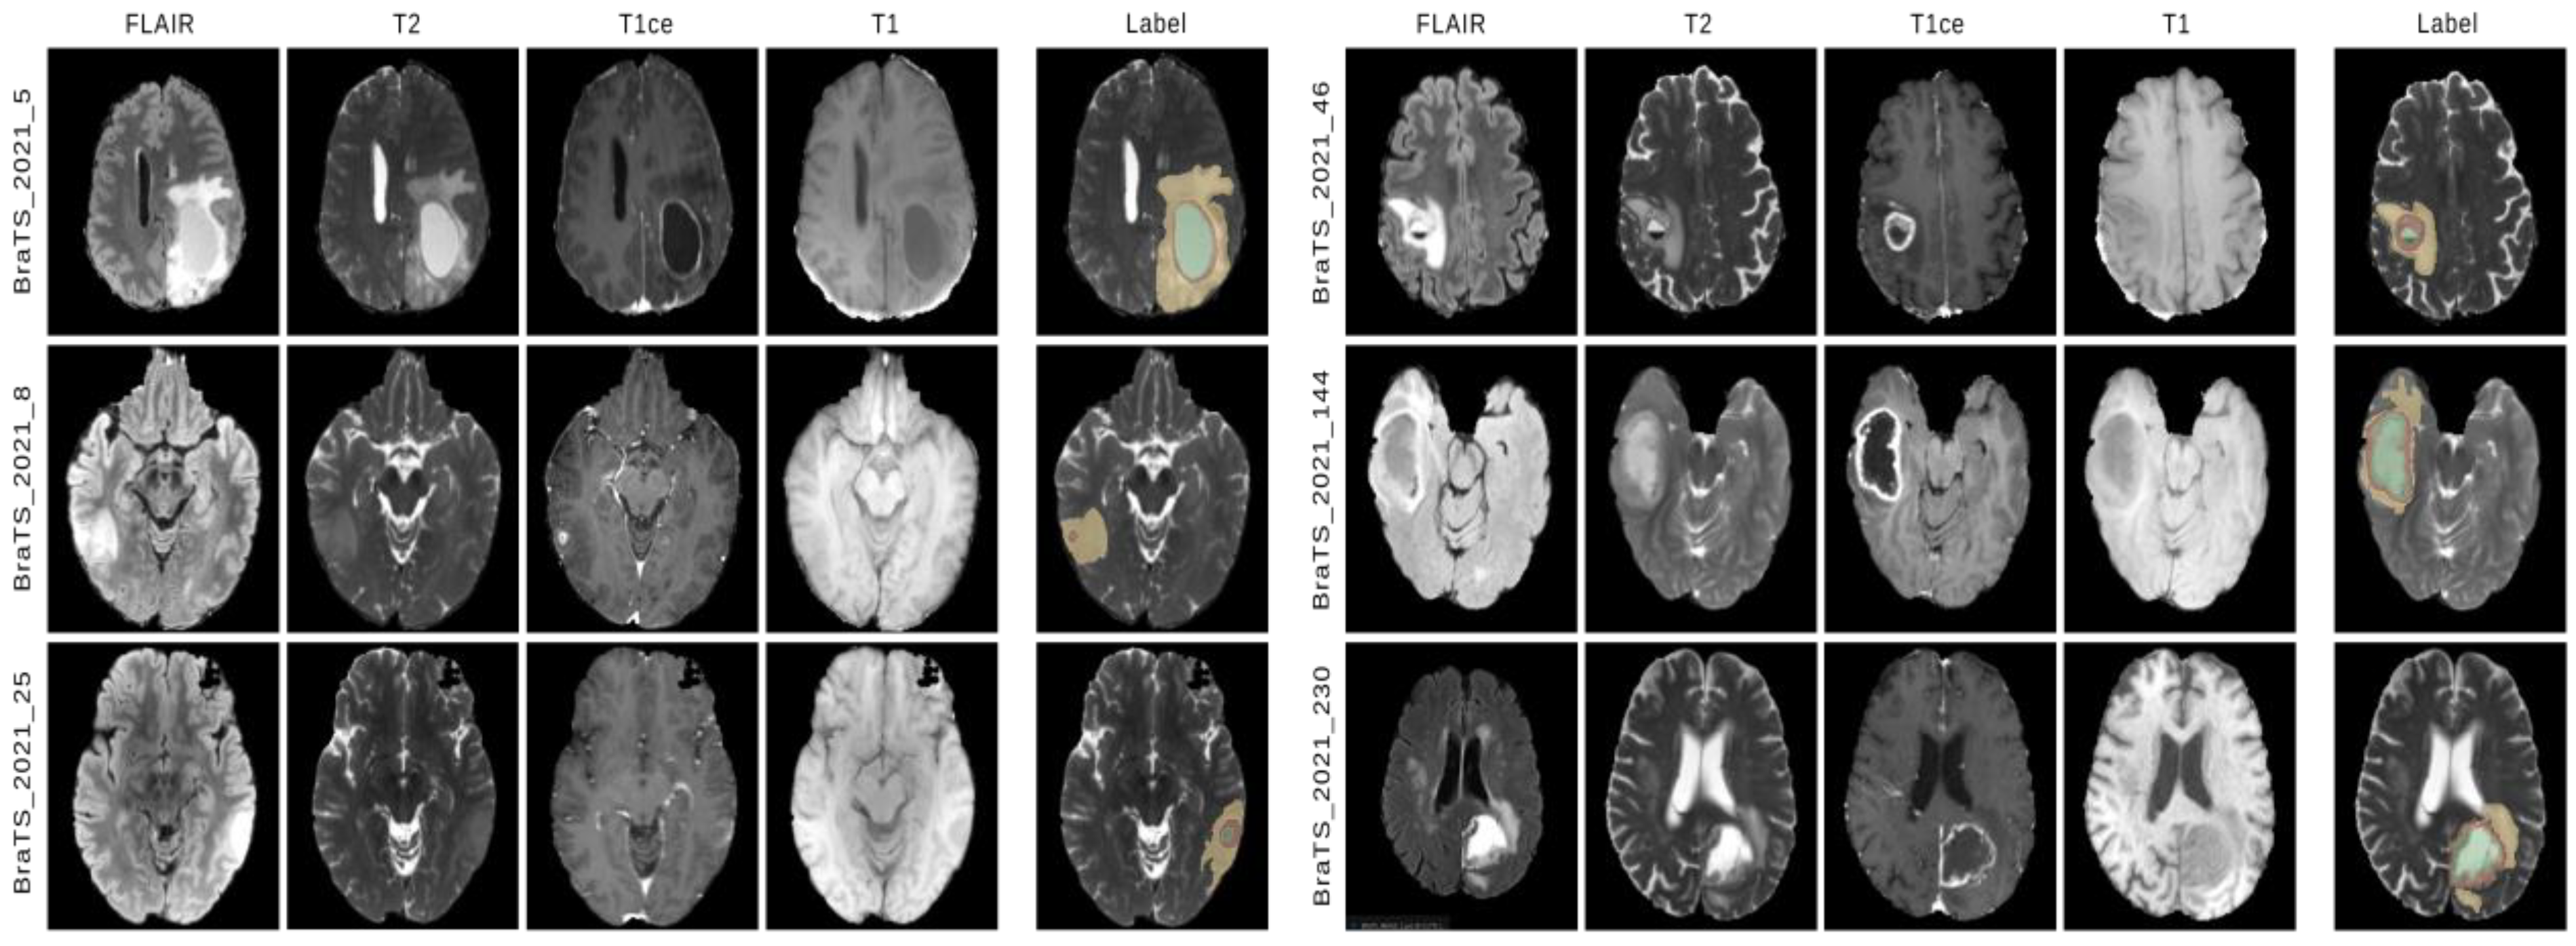

4.1. Dataset